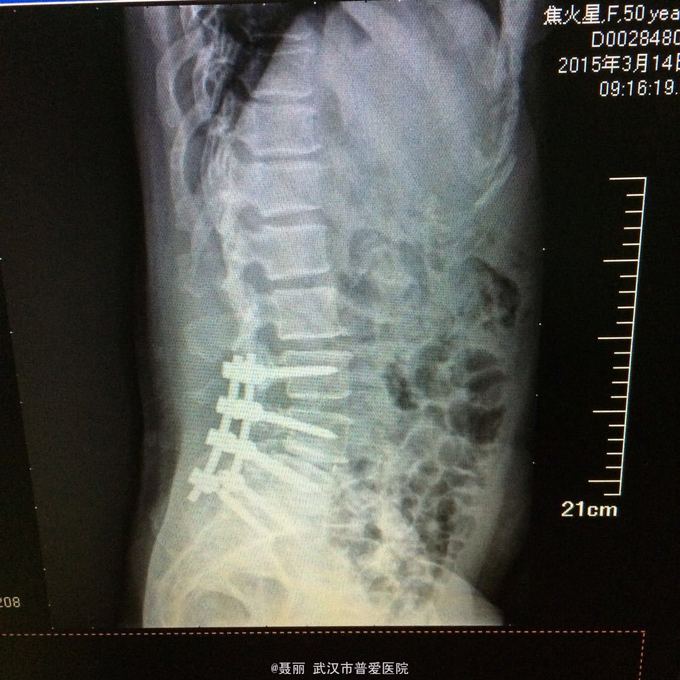

患者,女,51岁。 反复腰痛并间歇性跛行5年余,加重并左侧臀部2月余。 患者于5年前无明显诱因外伤诱因出现腰痛,不伴有双下肢麻木、乏力及间歇性跛行,卧床休息后好转,间歇发作,进行性加重。 既往史:有高血压病、糖尿病病史,否认有药物过敏

:L4/5棘突间轻压痛,叩痛,棘间左侧椎旁压痛;双下肢肌力、肌张力正常,病理反射未引出。 门诊资料:外院行腰椎CT检查示:L3-S1椎间盘膨出,L4椎弓崩裂并向前滑脱(重度)椎管狭窄。 入

入院诊断:、腰椎滑脱(L4/5 峡部裂性) 诊疗计划:1:完善有关检查2卧床休息,行改善微循环、3.腰椎后路复位减压植骨融合术

行改善微循环、3.腰椎后路复位减压植骨融合术 腰椎滑脱(L4/5 Ⅱ度)、腰椎管狭窄症(L3/4)、腰椎间盘突出症(L5/S1)查体双下肢感觉、活动无明显异常。双下肢末梢血液循环可。换药见伤口对合良好,无明显红肿渗出。伤口已拆线。嘱加强双下肢活动及功能锻炼,避免下肢深静脉血栓,主动及被动四肢活动,预防血静脉及床褥形成,加强腰背肌锻炼,适量康复功能锻炼。一个月后来复查伤口愈合好,疼痛没有,活动可